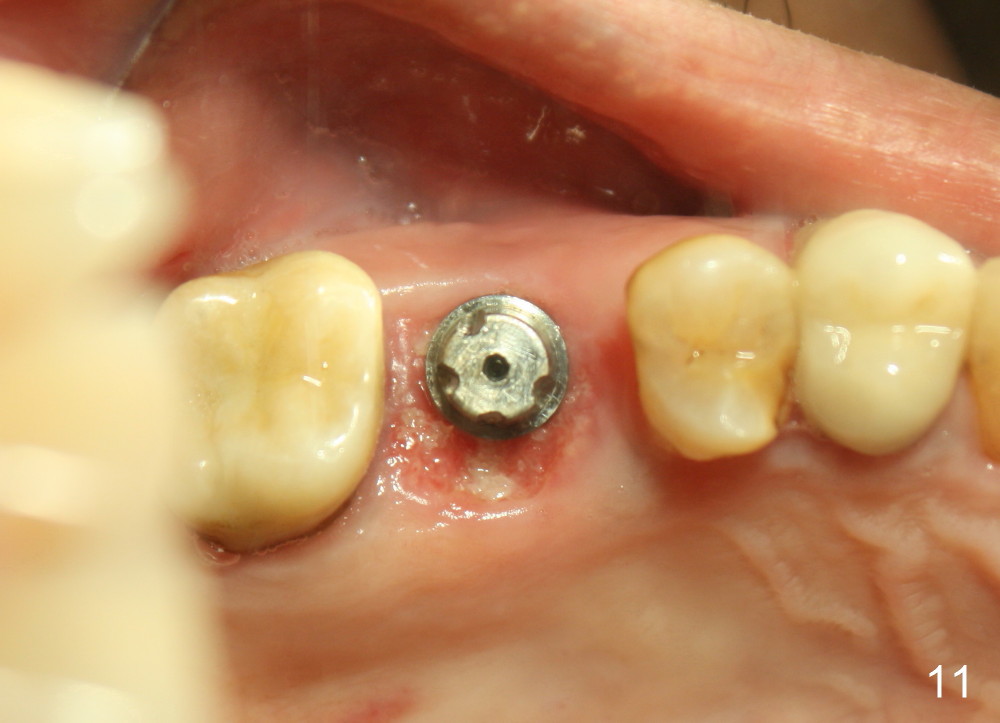

The 2nd perio dressing lasts for another two weeks. When it is removed in clinic, the wound heals; the implant is shown placed slightly buccally (Fig.11, occlusal mirror image). Buccal view shows that the fistula dissolves (Fig.12).